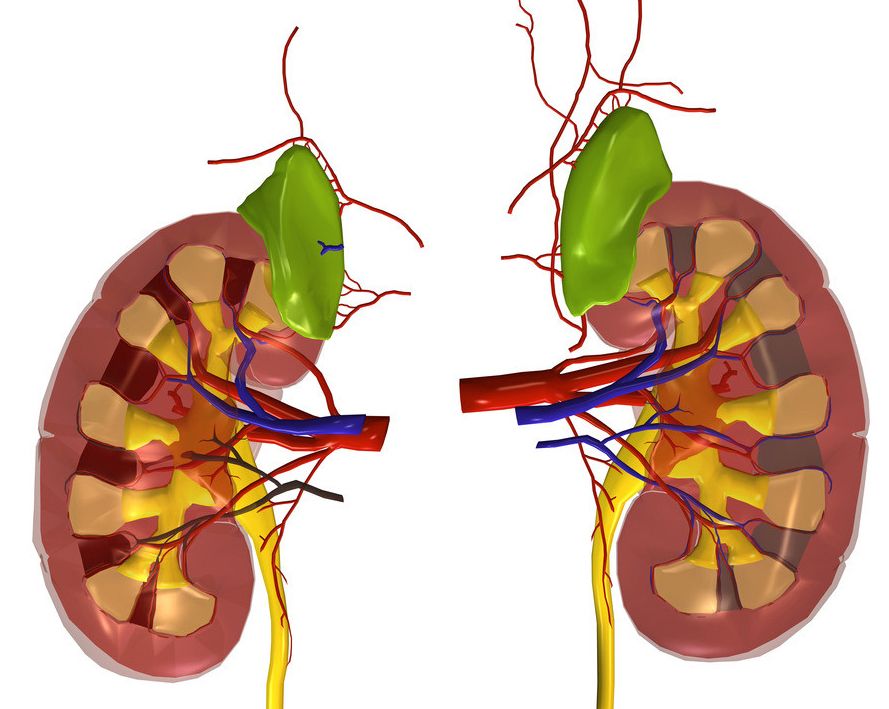

肾脏是人体的重要器官,它的基本功能是生成尿液,借以清除体内代谢产物及某些废物、毒物,同时经重吸收功能保留水份及其他有用物质,如葡萄糖、蛋白质等,以调节水、电解质平衡及维护酸碱平衡。

肾脏同时还有内分泌功能,为机体部分内分泌激素的降解场所和肾外激素的靶器官。肾脏的这些功能,保证了机体内环境的稳定,使新陈代谢得以正常进行。

肾脏是人体的重要器官,它的基本功能是生成尿液,借以清除体内代谢产物及某些废物、毒物,同时经重吸收功能保留水份及其他有用物质,如葡萄糖、蛋白质等,以调节水、电解质平衡及维护酸碱平衡。

肾脏同时还有内分泌功能,为机体部分内分泌激素的降解场所和肾外激素的靶器官。肾脏的这些功能,保证了机体内环境的稳定,使新陈代谢得以正常进行。